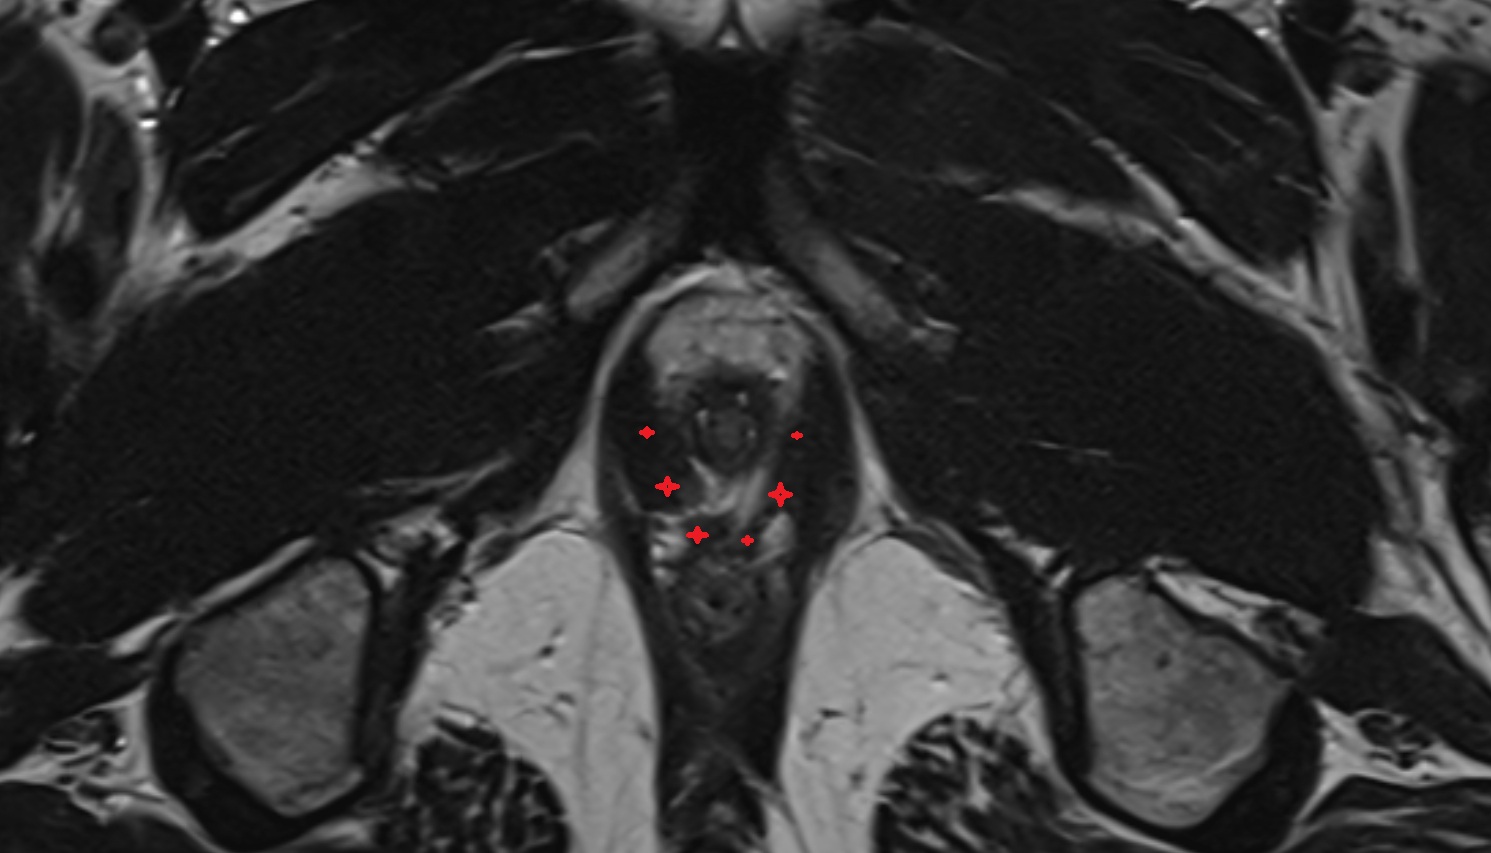

- Peripheral zone of prostate

- Anterior Fibromuscular Stroma of prostate

- Central zone of prostate

- Transitional zone of prostate